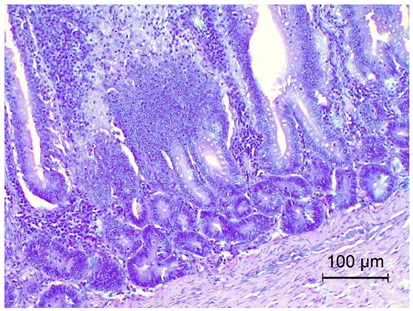

Table 4. Histopathology results of Pekin ducks with short beak and dwarfism syndrome (SBDS).

OrgansSBDS GroupNo. of Figs

TongueKeratinisation on the surface of the tongue.

Degeneration of the tongue along with ulceration.

Inflammatory infiltrate heterophilic cells.

Proliferating blood vessels around the inflammation.

Applsci 14 08637 i002